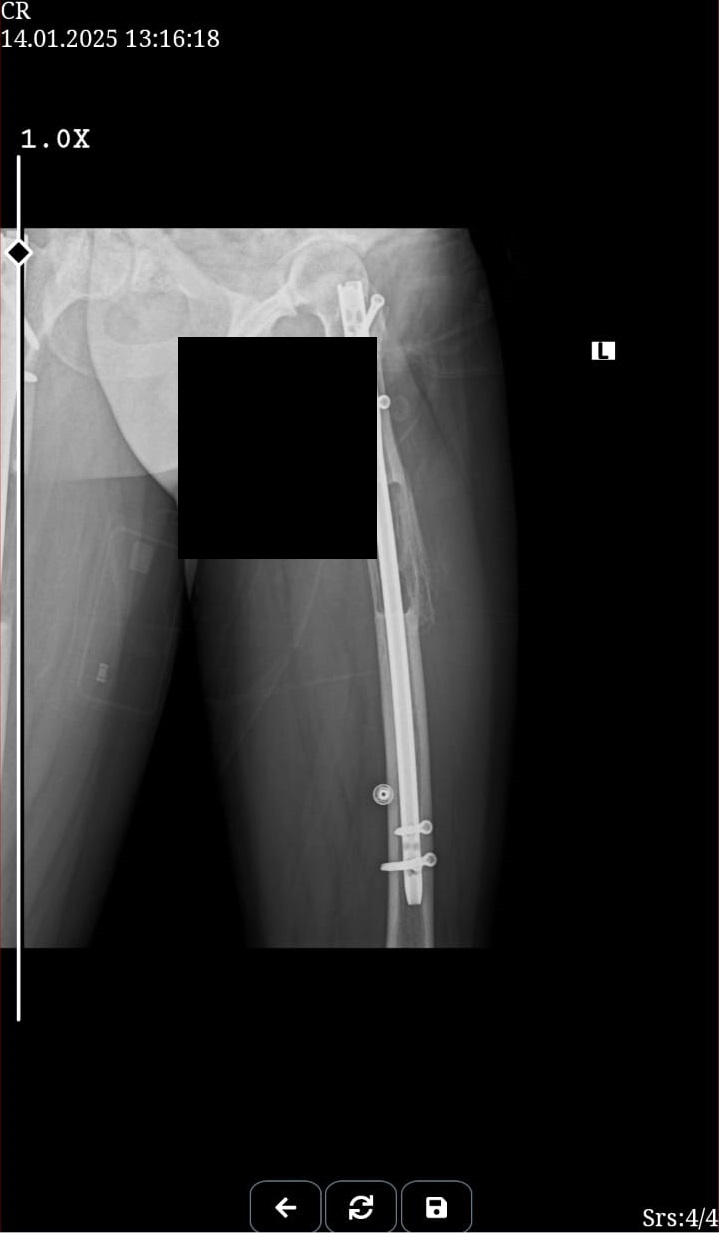

My new xrays that show bone formation.Attachments:

This is my after fixator removal xray00 -